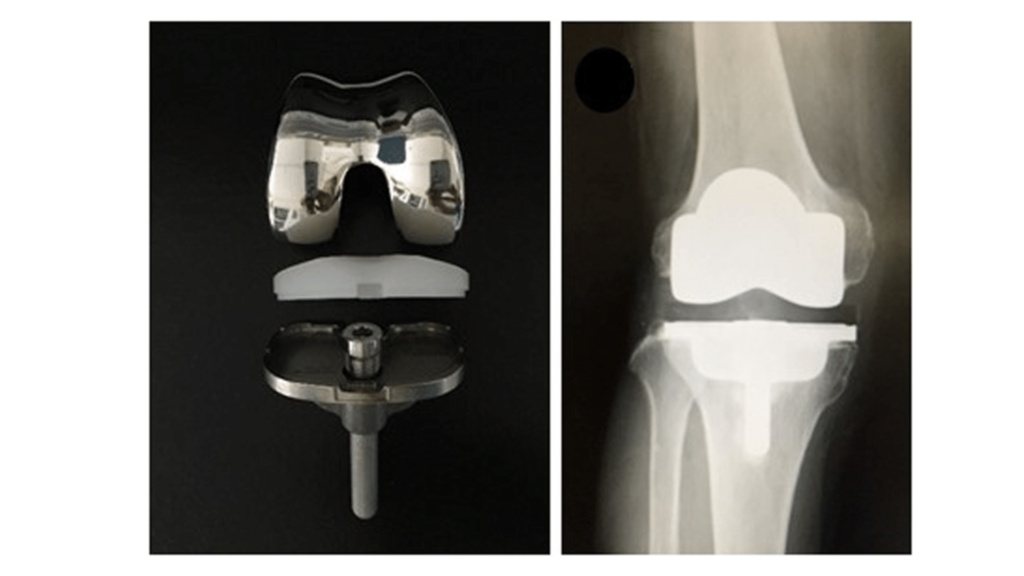

- The Posterior Cruciate-Retaining (CR) knee replacement is a popular choice for patients undergoing total knee replacement surgery. This technique is designed to keep the muscles or tendons intact, which helps maintain more natural knee movement and function.

- One of the biggest advantages of the CR knee design is that it offers superior outcomes in terms of stability and range of motion. Since the muscles or tendons remain, the knee continues to have its natural biomechanics, leading to a more comfortable and natural walking experience. Patients often report that their knee feels more like their original knee, making daily activities easier.

- Additionally, the CR design helps in reducing stress on the implant, which may lead to better longevity of the knee replacement. It also provides a smoother motion, reducing the chances of knee stiffness post-surgery.